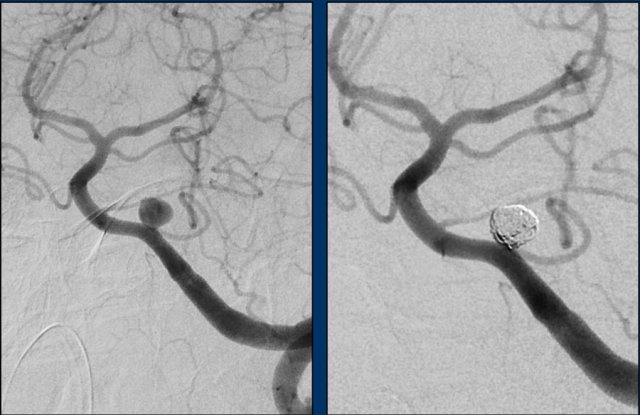

This patient underwent a digital subtraction angiography (DSA) and subsequent coiling.

The DSA showed a saccular aneurysm of the left PICA of 6 mm in maximal diameter with a short, narrow neck.

The images show DSA before and after coiling of the aneurysm.

The PICA, nidus and abnormal draining veins (together forming the AVM)  still show contrast enhancement.

It was decided not to treat the AVM directly and to opt for follow-up and possibly operative exploration in the future.